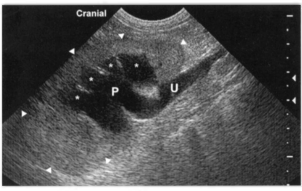

Рис 5. Обструктивный гидронефроз. Изображениеправой собаки с обструкцией мочеточника, вызванной конкрементом, продольная проекция. Обратите внимание на то, что дилатированные рецессусы (*) округлой формы и частично разделены гиперэхогенными перегородками, содержащими внутридольковые артерии и вены. Также визуализируется расширенная проксимальная часть мочеточника (U),сообщающаяся с лоханкой (Р)